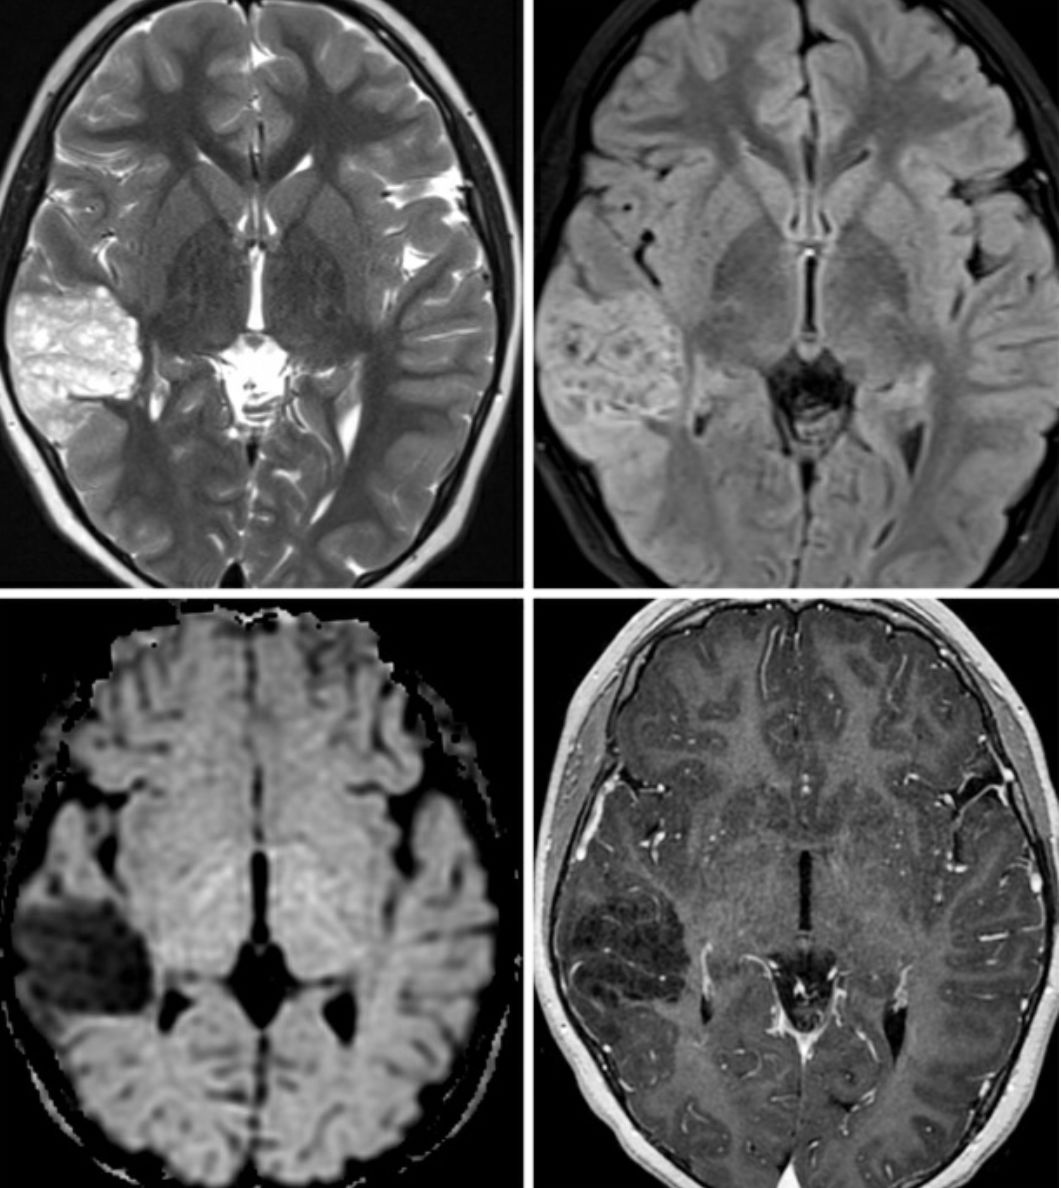

图1. 此例DNET患者的病变位于右侧颞叶外侧,侵及皮层和白质。在T2加权相(左上)和FLAIR加权相(右上)上呈典型的囊泡样改变。病变比较局限,临近皮层增厚或发育不良。在DWI加权相(左下)上呈低信号,提示肿瘤细胞含水量少。T1增强加权相(右下)上肿瘤未见明显强化。

(1)T1加权相:分叶状,泡状低信号肿瘤

(2)T2加权相:呈高信号泡状表现

(3)FLAIR相:信号多变,临近脑组织水肿少见

(4)T1增强相:常无强化效应

(5)DWI相:弥散不受限